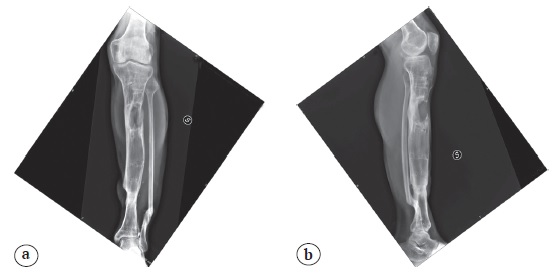

We present the case of a 17-year-old patient who suffered an open fracture of the left femur and left leg following a motorcycle accident in January 2017 (Figure 1).

Figure 1. X-rays show a diaphysis fracture of the right femur (a) and fracture and bone defect of the distal third of the tibia and fibula (b)

Initially the treatment was begun in another hospital. An external fixator for damage control orthopedics (DCO) was applied, for both femur and tibia. Surgical debridement of soft tissue and bone was performed to the distal third of the leg. A flap was set up to cover the loss of substance as soon as the inflammation rates returned to normal. After 4 weeks, the temporary leg external fixator was converted with the Ilizarov fixator. An antegrade bifocal bone transport with proximal metaphyseal osteotomy was chosen to fill a 10 cm bone defect (Figure 2).

Figure 2. AP and lateral X-rays showing first Ilizarov fixator: a — a yellow line makes evident the level of proximal metaphyseal osteotomy; b — a yellow arrow indicates the distal part of tibial tubercle